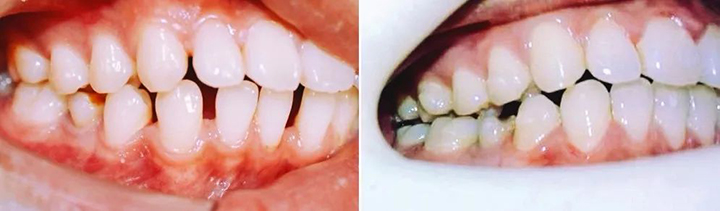

上图就是矫正前后牙齿的对比照,欢迎观看右边照片多一点!

那就是54副牙套带来的一口重生的白牙。

『 排齐上下前牙,关闭前牙散在间隙 』

——矫正目标临近达成,再有4副就能收工,完美!

完整的观察一下目前达到的矫治效果,会发现真的很棒!